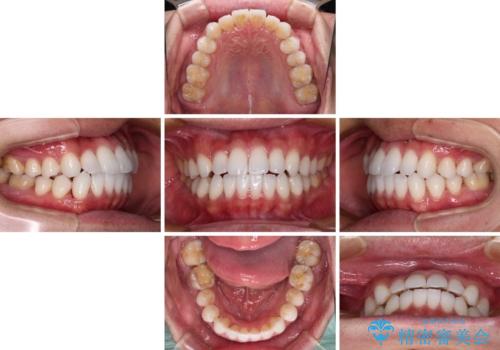

前歯のクロスバイトを改善 インビザラインによる矯正治療

今回は、ワイヤー装置を併用することなく治療を行い、トラブルなく、満足のいく歯列に整えることができました。

矯正治療の途中でホームホワイトニングを併用され、術前とは見違えるほどきれいな口元となりました。